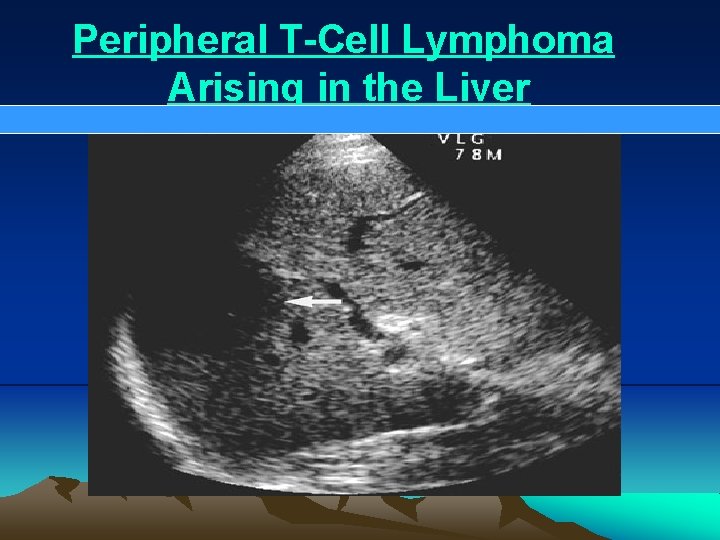

Peripheral T-Cell Lymphoma Arising in the Liver